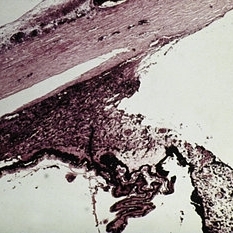

Slide 7-30

Feb 25 2019 by Lancaster Course in Ophthalmology

Pleomorphism, rather than polymorphism, characterizes a malignant lymphoma.

Condition/keywords: lymphoma, pleomorphism